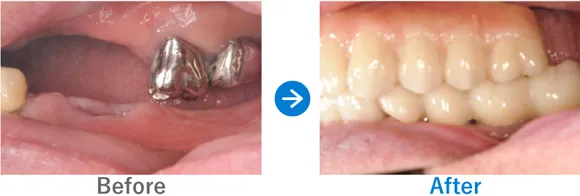

Case3

重度の歯周病を罹患された方。フルマウスインプラント治療直後に仮歯が入り感動されたケース

全顎上下共にブリッジ治療されている。重度の歯周病で歯がグラグラしている。

上下、ALLON4

5,884,000円(上下総額/内訳:上顎オールオン4(ノーベルインプラント4本)、下顎オールオン4(ノーベルインプラント4本)、3Dモデルガイド*、仮歯、セデーション、ボツリヌストキシン注射、3D模型、保証10年)

*単体のインプラントのガイドとは異なる、オールオン4専用のガイド

※当時の価格で現在とは異なる場合があります。

来院の背景

全体的に重度の歯周病に罹患しており、歯がグラグラしており抜けそうで咬めない、食事ができなく困っていた。インプラントを検討していたが他院で800万円〜900万円と聞いた。デンタルローンを申請。

治療結果

上下のALLON4を実施して治療同日に上下手術を行った。治療後すぐに仮歯が入ったので、とても喜んでいただいた。治療終了。メンテナンス来院継続中。

現在、セルフケアもしっかりされていて、メンテナンスも欠かさず来院していただいているため、インプラントは問題なく使えています。先日、横浜院で10年ぶりくらいにお会いしたのでご挨拶したら、とても喜んでくださりました。あの時インプラントの決断をして良かったと仰っていました。